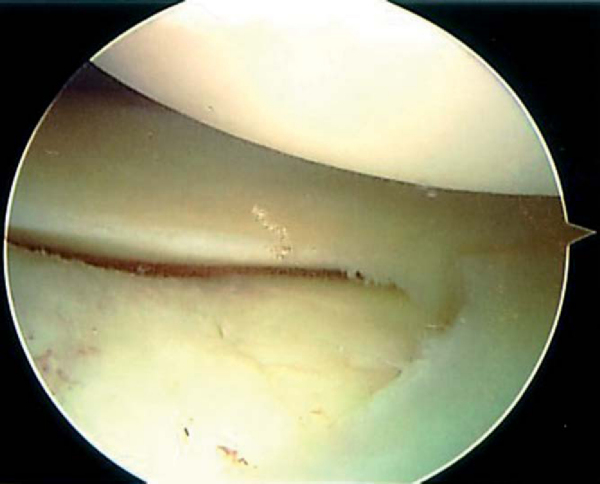

The medial compartment is entered by following the trochlea down into the intercondylar notch. A veil of tissue, the ligamentum mucosum, often covers the cruciate ligaments (

Fig. 42-5

). This tissue is either pulled aside with a probe or removed with a motorized shaver. The substance of the cruciates and their visible insertions are carefully inspected. Again, a probe is valuable in assessing the tension of the ligaments.